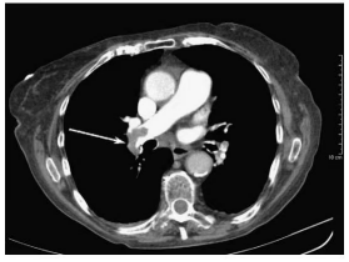

CTPA支气管动脉成像是肺栓塞诊断的首选方法,通过该检查能直接观察到栓塞,同时可以观察血管的形态及外周的变化。对于碘造影剂过敏的患者,可考虑磁共振肺动脉造影(MRPA)或者核素通气/灌注(V/Q)显像。而介入下肺动脉造影为一种有创检查方式,作为次选。